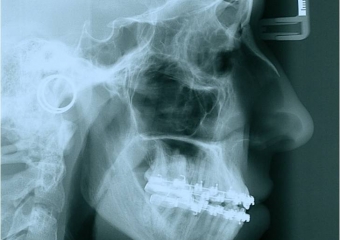

Telerradiografia de perfil inicial - Clínica Cliniface

Telerradiografia de perfil inicial